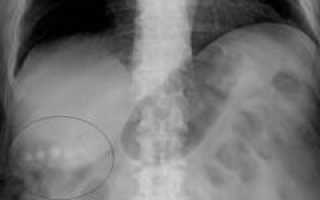

Рентгенография

Рентгенография — метод получения и анализа рентгеновских изображений. Изображения формируются рентгеновскими лучами, проходящими через исследуемую область тела и фиксируемыми на пленке. Источник излучения — рентгеновская трубка, расположенная перед объектом. Рентгенограмма создается благодаря различиям в плотности тканей: более плотные структуры поглощают излучение сильнее, что отображается на снимке темными участками, а менее плотные — светлыми.

Для точной диагностики рекомендуется проводить исследование в двух перпендикулярных проекциях — прямой и боковой. Это помогает избежать наложения теней и улучшает качество диагностики.

Типы рентгенографии:

- Обычная рентгенография. Основана на естественном контрасте тканей, обусловленном их плотностью.

- Контрастная рентгенография. Включает введение контрастных веществ в полости, органы или сосуды, которые по-разному поглощают рентгеновские лучи (например, кислород и углекислый газ поглощают слабее, а соединения йода и бария — сильнее). Это позволяет лучше визуализировать контуры органов.

- Обзорная рентгенография. Охватывает целый орган или группу органов (например, органы брюшной полости), позволяя оценить их расположение и размеры.

- Прицельная рентгенография. Фокусируется на конкретном участке или образовании в органе (например, киста печени).

Рентгенография безопасна, доступна и быстра. На современных аппаратах изображение можно получить за 10-15 минут. Контрастная рентгенография требует больше времени и подготовки из-за необходимости введения контрастного вещества и наблюдения за пациентом на предмет аллергических реакций.

На рентгенограмме можно выявить следующие изменения:

- Увеличение или уменьшение размеров органа. Увеличение может указывать на гепатит или панкреатит, уменьшение — на цирроз печени или спазмы кишечника.

- Смещение органа. Обычно связано с увеличением соседнего органа, часто наблюдается при панкреатите или новообразованиях.

- Наличие затемнений. Указывает на опухоли в печени, кишечнике или других органах, так как ткани новообразований имеют более высокую плотность.

- Наличие кольцевой тени. Может свидетельствовать о абсцессе или кисте, указывая на границу пораженного участка.

- Непроходимость. Важный диагностический признак, может быть сосудистым или органным, встречается при тромбозах или опухолях.

- Изменение рисунка слизистой оболочки. Часто наблюдается при воспалительных или инфекционных заболеваниях желудка и кишечника.

- Изменение контуров органа. Ненормальные контуры могут указывать на опухоли или язвы в различных органах.